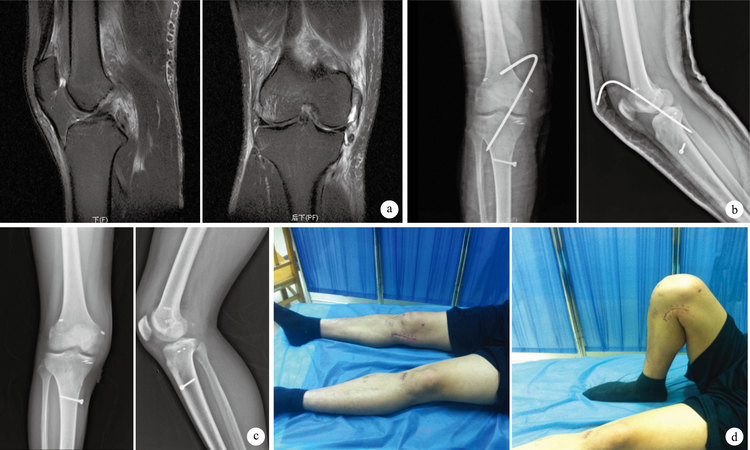

術后患者切口均Ⅰ期愈合,無感染等手術相關并發癥發生。患者均于術后6周開始膝關節功能鍛煉,其中7例行麻醉下手法松解(其中傷后2周內手術者4例,2~3周內手術者2例,3周后手術者1 例)。22例均獲隨訪,隨訪時間12~48個月,平均27.8個月。術后12個月,前、后抽屜試驗,Lachman試驗、反Lachman試驗,內、外翻應力試驗均呈陰性。膝關節活動度提高至(121.3±7.9)°,Lysholm評分達(87.2±6.1)分,與術前比較差異均有統計學意義(t=30.061,P=0.000;t=24.642,P=0.000)。其中,傷后3周內手術者膝關節活動度及Lysholm評分分別達(119.0±16.3)°及(89.2±1.6)分,3周后手術者分別為(126.3±7.5)°及(83.5±2.1)分。見圖 1。